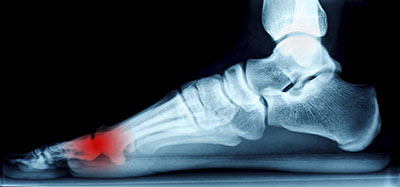

Morton’s neuroma may develop when the tissue around one of the nerves leading to your foot begins to thicken. When this occurs, you may experience some discomfort as if you were standing on a pebble stuck in your shoe. Most symptoms will not appear outwardly and will be experienced in the form of a sharp, burning pain in the ball of the foot, as well as a stinging or burning feeling in the toes that may sometimes lead to numbness.